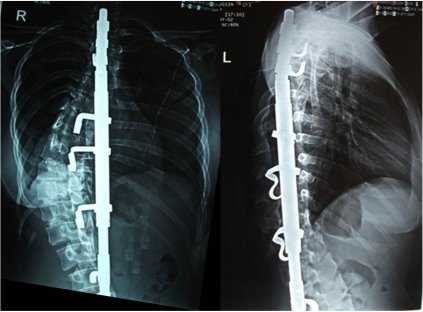

Клинический пример: больная Н., 1999 г.р., прооперированная по поводу сколиотической болезни (рис.1-4):

Рис.4. Передняя и боковая спондилограмма после операции